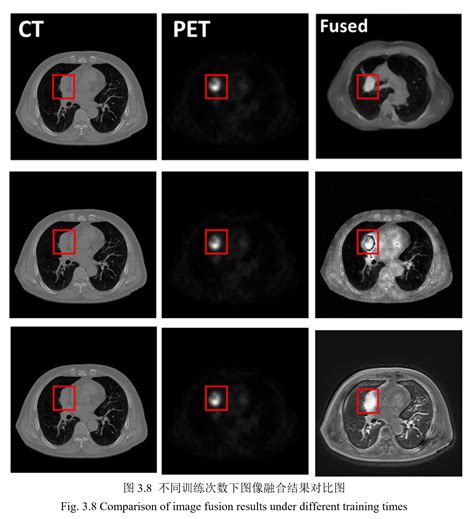

When these two technologies are combined into a single Pet Ct machine, the results are fused together. This allows doctors to pinpoint the exact location of a biological abnormality and observe its physical size and shape simultaneously. The fusion of this data is what makes it a gold standard in modern diagnostics.